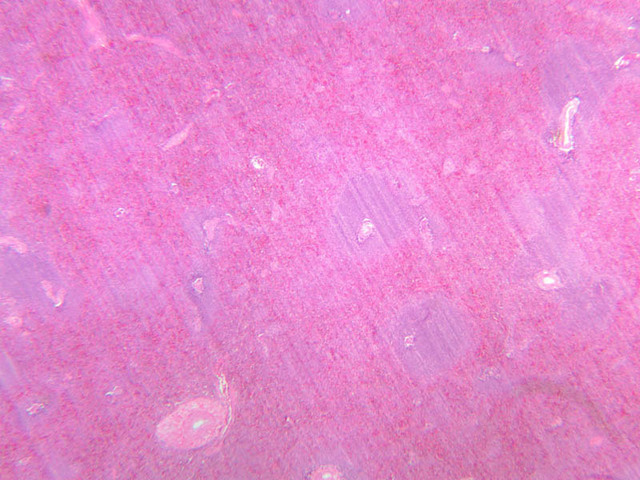

The spleen is structurally arranged to filter out foreign agents, and to destroy worn-out red blood cells. To accomplish this, the blood leaves the blood vessels and passes through a meshwork of reticular tissue where phagocytic cells can pick out bacteria and antigenic materials as well as worn-out red blood cells.

Sections through the spleen (slides A-36, aniline blue [2.5x, 10x, 20x-labeled, 40x] [2.5x, 10x-labeled, 20x-labeled, 40x]; A-37, retic [2.5x, 10x, 20x-labeled, 40x]; A- 37, H&E [2.5x-labeled, 10x, 20x, 40x]; A-38, H&E [10x, 20x, 40x]; A-39, H&E [2.5x, 10x, 20x, 40x]) show a thick investing capsule composed of collagenous tissue and smooth muscle, typically covered with mesothelium. In slide A-36 muscle and collagen are brightly stained. The capsule and mesothelium completely surround the organ and the fibrous portion enters the splenic substance at the hilus around the splenic arteries and veins forming trabeculae of fibromuscular tissue within the splenic substance. This fibromuscular tissue enables the spleen to expel blood by contracting. Identify trabeculae as fibrous partitions in the section and look for blood vessels within them.

Where the trabecular arteries pass into the splenic pulp, they become invested by a sleeve of lymphoid tissue. This lymphatic tissue collectively forms the white pulp of the spleen (A-36 [2.5x, 10x, 20x, 40x]). It also is referred to as the periarterial lymphatic sheath or PALS. On an H&E stained section (A-38 [2.5x, 10x, 20x, 40x] [2.5x, 10x, 20x, 40x]) the white pulp will appear as basophilic clumps of lymphoid cells. The arteries of the white pulp are called central arteries, although they may be displaced to one side of the lymphoid sleeve by the presence of a nodule. The majority of cells forming the PALS are T lymphocytes. In places the covering of lymphatic tissue is enlarged due to the presence of lymphoid nodules (splenic or Malphighian corpuscles) which are comprised predominantly of B lymphocytes.

The remainder of the cellular mass in the spleen is red pulp (A-38 [10x, 20x, 40x]), made up of red and white cells of the blood enmeshed in the reticular tissue of splenic cords and present in the splenic sinuses. After passing through the PALS, the trabecular arteries branch to form smaller arterial vessels known as penicillar arterioles which narrow, forming arterial capillaries that empty into the cords of the red pulp (open circulation) or into the venous sinuses (closed circulation). In the splenic sinuses the cells of the blood are exposed to red pulp macrophages. The splenic sinuses eventually become confluent to form veins that enter the trabeculae and gradually merge meeting in the hilus to form splenic veins.

Examine the composition of the red pulp tissue. The three dimensional structure of the red pulp is analogous to Swiss cheese with the holes being the venous sinuses and the cheese being the parenchyma (i.e. splenic cords). On slide A-36 which is stained with Mallory's aniline blue locate examples of the splenic sinuses ([2.5x, 10x, 20x, 40x-labeled] [10x, 20x, 40x]). The walls of the splenic sinuses consist of adjoining specialized endothelial cells whose nuclei in many cases stand out from the wall in a bead-like fashion. The basement membrane of the epithelial cells stains blue revealing the sinuses quite nicely. Usually the sinus lumen is filled with red cells and leukocytes. The skeletal framework of the cords is provided by a network of reticular fibers. As above, the reticular cells are best seen using a reticular fiber stain (slide A-37 [2.5x, 10x, 20x, 40x-labeled]). Look for the large pale nuclei of reticular cells that have darkly stained reticular fibers. Fibers run irregularly in the cords, but clearly outline the sinuses around which they are wrapped. Notice on this same slide that there is much less reticular tissue in the white pulp than the red. The splenic cords occur around the sinuses and are distinguished by the presence of disintegrating red blood cells undergoing phagocytosis.

Here's a little histopathology: Observe slide A-40 (H&E [2.5x, 10x, 20x, 40x]). In this slide the corpses of red blood cells appear brown and can be seen littered throughout. These residual RBCs are referred to as hemosiderin. Slide A-39 (H&E [2.5x, 10x, 20x, 40x]) was prepared from a patient undergoing chemotherapy. How does the white pulp in this slide differ from the normal spleen, slide A-38?